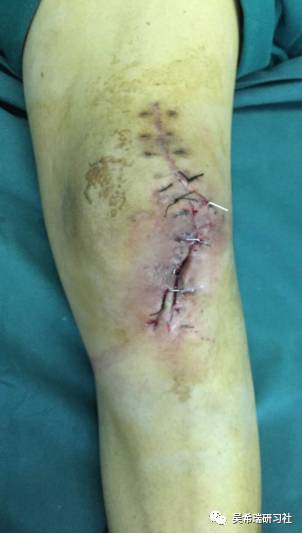

髌骨手术后继发感染40天髌韧带外露

TIPS:清创后再固定伤口用抗生素骨水泥感染得到控制后皮肤牵张闭合伤口2个月内手法松解关节,骨牵引维持5天